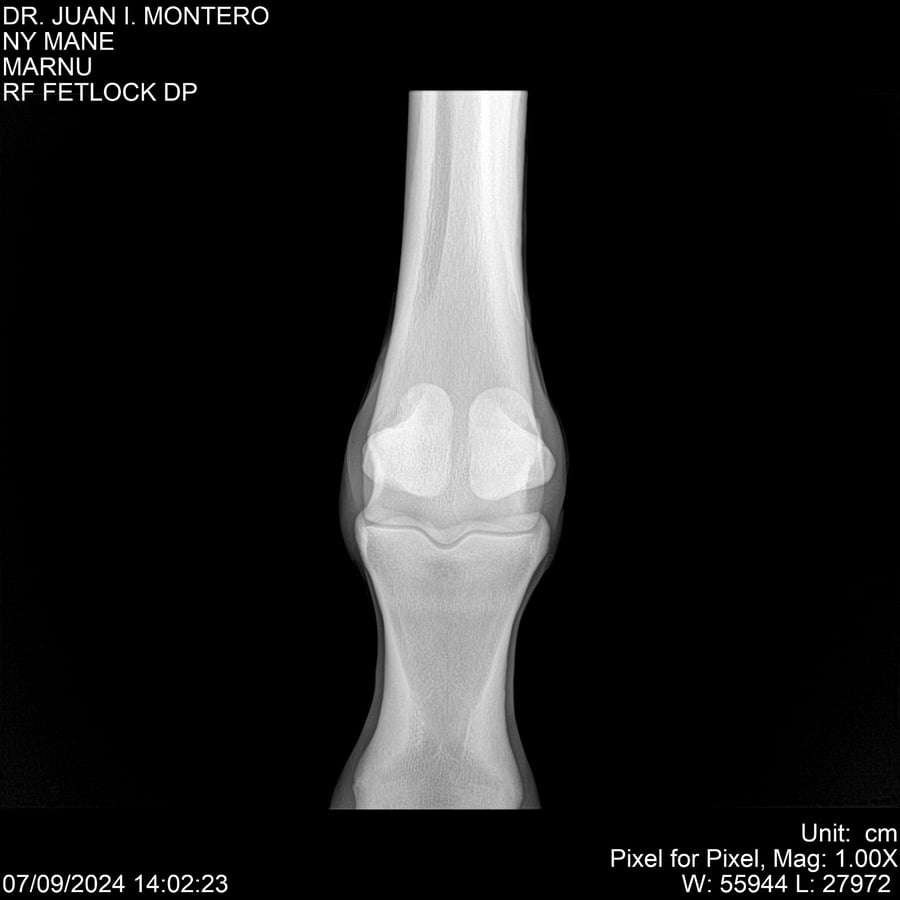

LOTE 20, NY MANE Lote Anterior Volver al remate Lote Siguiente Ficha Contacto Montevideo - Ficha del Lote Identificador: #282520 Categoría: Yeguarizos 76 Visualizaciones ClicData Contacto Empresa: Abelenda N. R., Walter Hugo Nombre*: Teléfono* : E-mail* : Mensaje Enviar Registrese gratis Este contenido Exclusivo está disponible sólo para usuarios registrados Ingresar